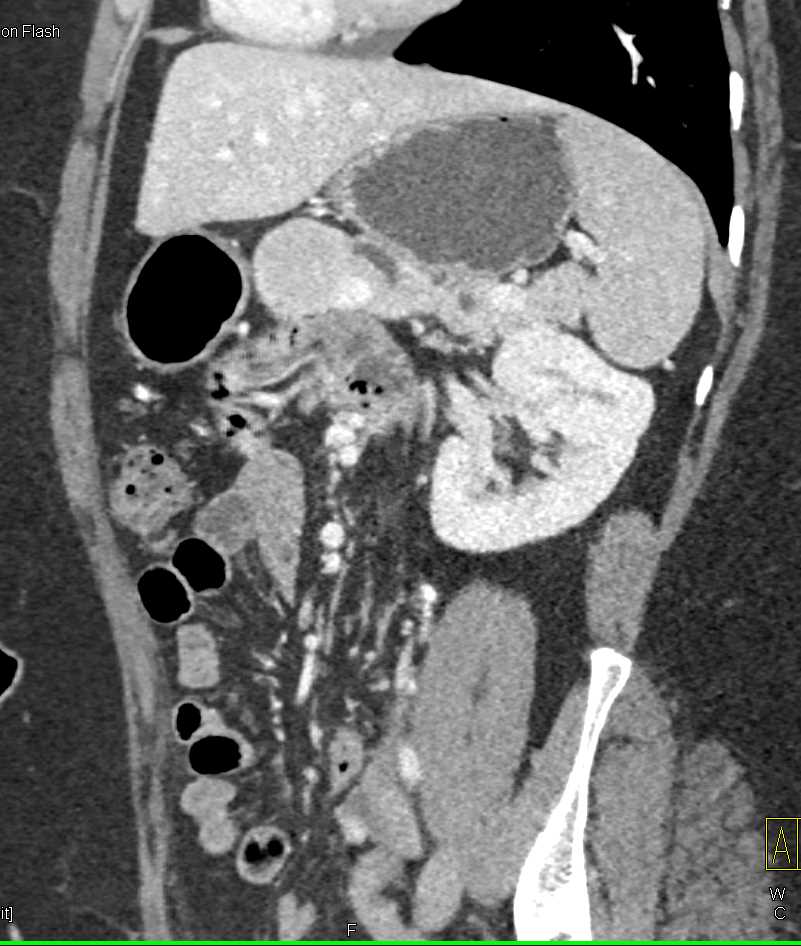

Neuroendocrine Tumor Body of Pancreas